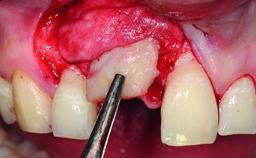

A 32-year-old female Caucasian patient with a compromised maxillary right central incisor was referred to us by a general dentist. Her chief complaints were discomfort and mobility of tooth 11 with unsatisfactory esthetics due to discoloration. The patient reported a previous trauma, some years earlier, as the origin of pathology on the afflicted tooth. Anamnesis was negative for any other dental or periodontal pathology in the remaining dentition. The patient did not take any medication and reported to be a light smoker (5–10 cigs/day). She had high esthetic expectations of her treatment. The extraoral examination revealed a high smile line with full exposure of her maxillary teeth and surrounding soft tissue in the area between the second premolars.